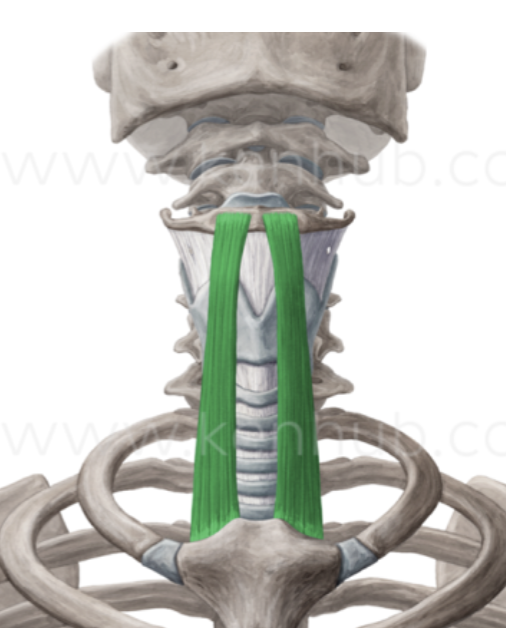

What is this muscle?

Sternohyoid (depress hyoid)